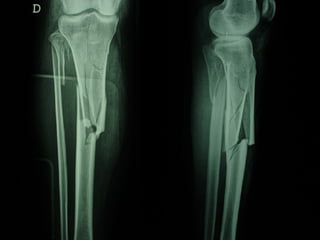

Dal Gennaio 2000 al Febbraio 2006 abbiamo trattato 167 fratture chiuse  con placca percutanea  in 164 pazienti :  27 lesioni diafisarie di gamba, 12 piloni tibiali ,  11 fratture prossimali di tibia, 36 fratture sovracondiloidee di femore, 17 fratture diafisarie di femore, 43 fratture metaepifisarie prossimali di omero, 21 diafisarie d’omero.  156 guarigioni 8 fallimenti

Dal Gennaio 2000 al Dicembre 2005 27 placche LISS di femore